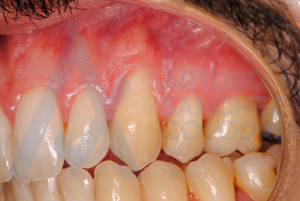

Aquí puede observarse la colocación de la membrana regenerativa

Tras la cirugía mucogingival realizada por el Dr. Arturo Sánchez Colodro en la primera parte de la boca (paciente aún en fase de tratamiento):